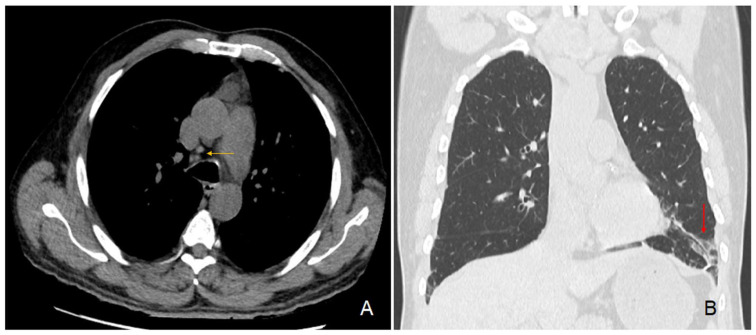

In parallel, the preoperative chest CT scan showed incidental signs of slight usual interstitial pneumonia characterized by fibrous reticulations and bronchiolectasis located at the pulmonary bases and small mediastinal lymphadenopathies (Figure 3). Since his surgery, the patient regularly consulted for recurrent pyrexia and chills, nocturnal coughing and wheezing, epistaxis, along with a 7 kg weight loss over 6 months. Subsequently diagnosed with asthma and sleep apnea syndrome, he was treated with inhaled fluticasone-vilanterol 92/22 μg and a continuous positive airway pressure device. A brain CT scan showed signs of chronic pansinusitis. Furthermore, our patient regularly consulted for recurrent episodes of pruriginous eczematiform rashes. Skin biopsies remained unspecific.

Progressive renal dysfunction is likely multifactorial, having first experienced several episodes of obstructive acute kidney failure. Our patient also experienced episodes of tubulointerstitial nephritis, characterized by visible lymphocytic infiltration in the renal biopsy (Figure 3). Granulomas were not found in the renal sections examined, consistent with the literature, although they may have been present in other segments of the kidney that were not analyzed.